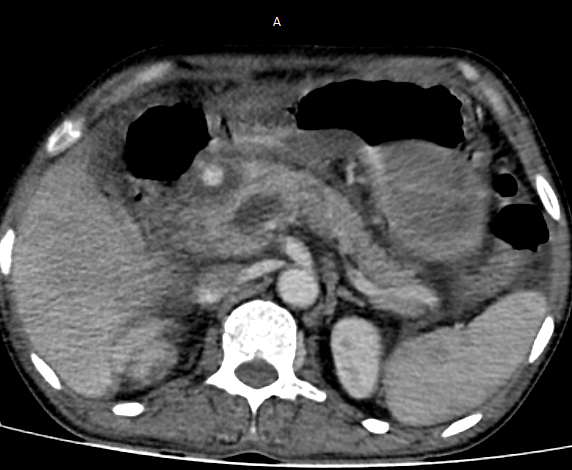

A straightforward GDA Pseudoaneurysm embolization. But Angiogram looks like this, how would you proceed further? #iRad #MedTwitter @SRajesh_IR @karananandpara @iRadRock @keithppereira @ChengaziMD @Murthy_CS_ @lenonjdee @PulkitRangarh @drochohan @ChengaziMD